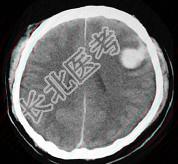

- 单项选择题女,52岁, 有高血压病史,半小时前突感头晕, 剧烈头痛,摔倒在自家楼下, CT检查如图所示,最可能的诊断是 ( )

E、脑出血